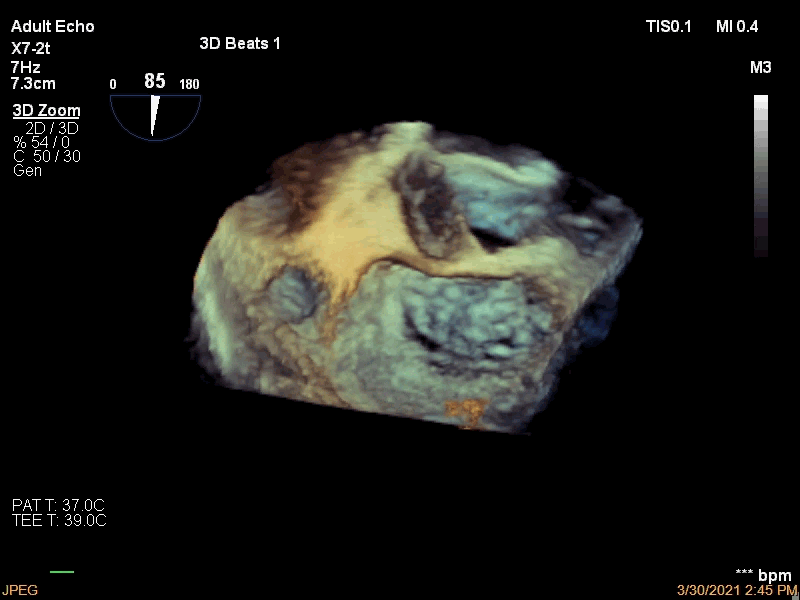

3月30日患者先在全麻下进行TEE(经食道超声心动图)再次评估瓣膜情况(视频4、视频5、视频6 ),确定为二尖瓣前组乳头肌断裂致二尖瓣前瓣脱垂并重度返流,其脱垂部位、瓣叶结构、瓣口面积等适合进行二尖瓣夹合术。术中IABP辅助,ECMO湿备,穿刺右侧股静脉,在TEE指导下顺利穿刺房间隔,随后送入二尖瓣夹合系统,在超声指导下于二尖瓣A2/P2区植入一枚Mitraclip XTR夹合器(视频7),术后TEE评估返流程度从5+降至1+(视频8 ),夹合结果满意,二尖瓣呈双孔启闭(视频9 ),术后二尖瓣平均跨瓣压差1mmHg(图1),收缩期肺静脉返流消失(图2 ),手术总耗时80min。香港亚洲医疗中心林逸贤教授通过视频连线进行手术全程技术支持。

视频9